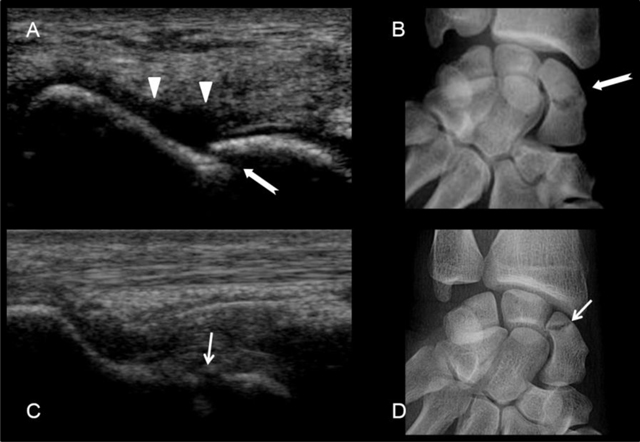

Figure 9

Scaphoid fractures. (A) and (B) transcortical fracture of the waist of the scaphoid. See the cortical disruption (white arrow) and the subperiosteal hematoma (arrow heads). (C) and (D) fracture of the proximal pole of the scaphoid with cortical disruption (small white arrow).